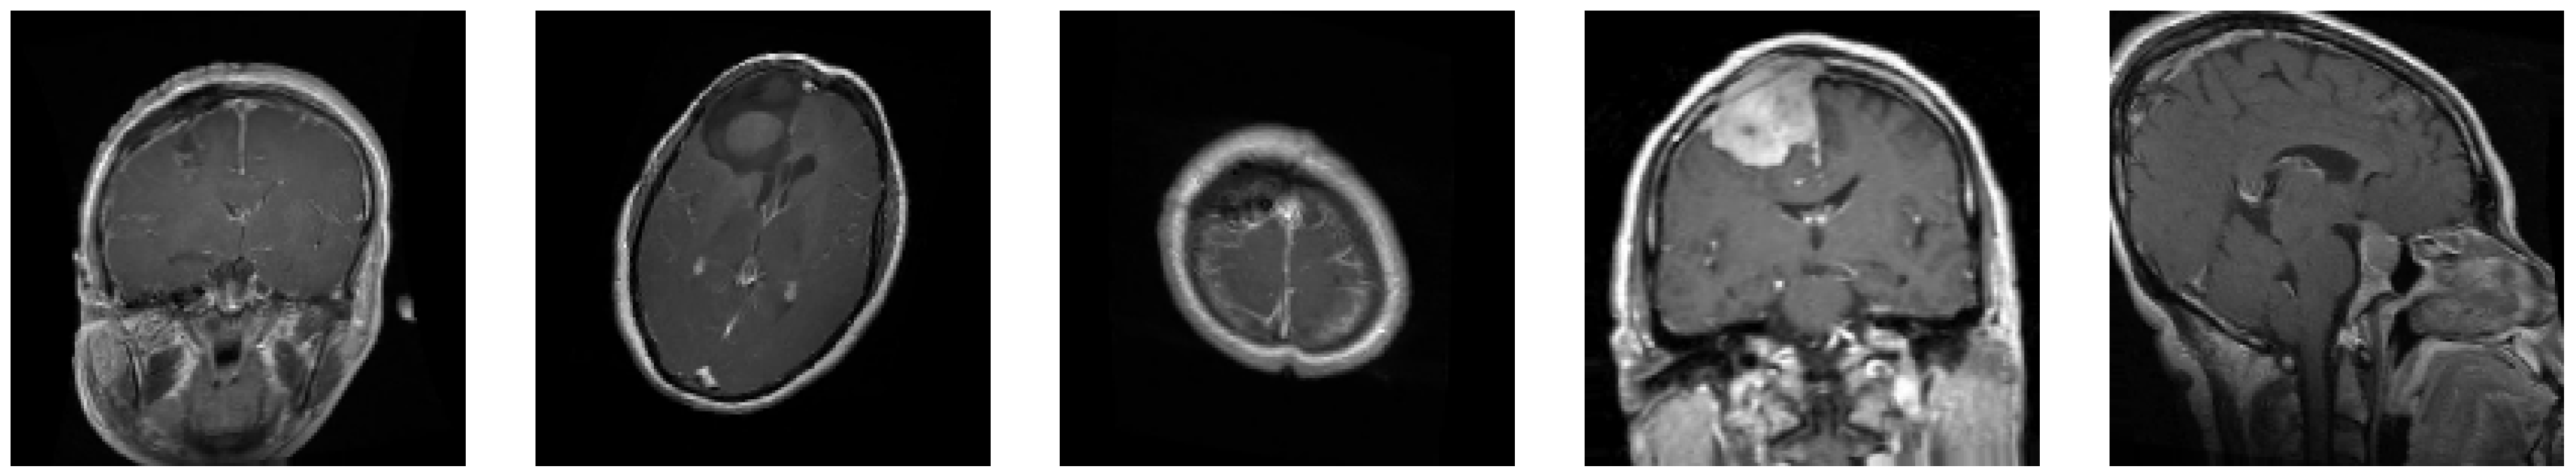

3.1. Dataset Overview

- Glioma: Cancerous tumors in glial cells.

- Meningioma: Non-cancerous tumors originating from the meninges.

- No Tumor: Normal brain scans without detectable tumors.

- Pituitary: Tumors affecting the pituitary gland, which can be either cancerous or non-cancerous.